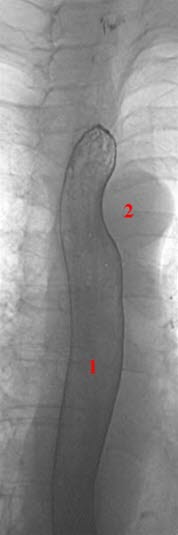

Midtre del av øsofagus framstilt med dobbel-kontrast teknikk

1. Øsofagus

2. Arcus aorta